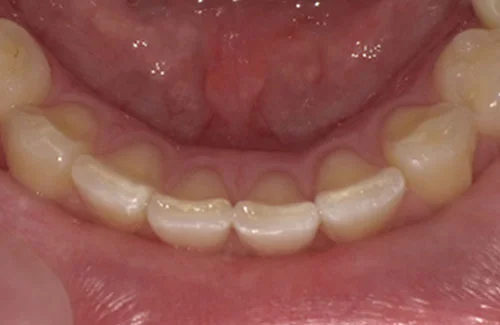

<症例5>上の前歯が飛び出しているお悩み

下の歯のガタガタと若干の前歯のズレの矯正でした。

アーチが綺麗に揃ったことにより見た目が改善されたほか、ステインや歯石も付きにくくなりました。

患者様と症状

主訴:下の歯がガタガタ

性別・年齢:20代女性

問題点:叢生、ディープバイト

診断:前歯部の叢生を伴うアングルⅠ級の不正咬合

主なリスク:矯正中一時的に咬合しにくくなる、歯肉退縮

症状:叢生(そうせい) 過蓋咬合(かがいこうごう)

治療内容

治療期間:3ヶ月

治療費用:330,000円(税込)

プラン:8枚コース/アーリープラン

抜歯:無し

再診治療費:無し

追加治療費:無し

保定装置費:無し

治療前後の写真